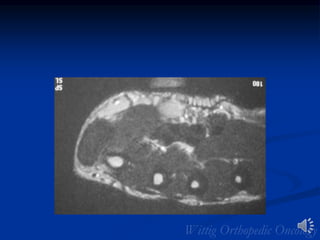

MFH Foot

MFH of Foot